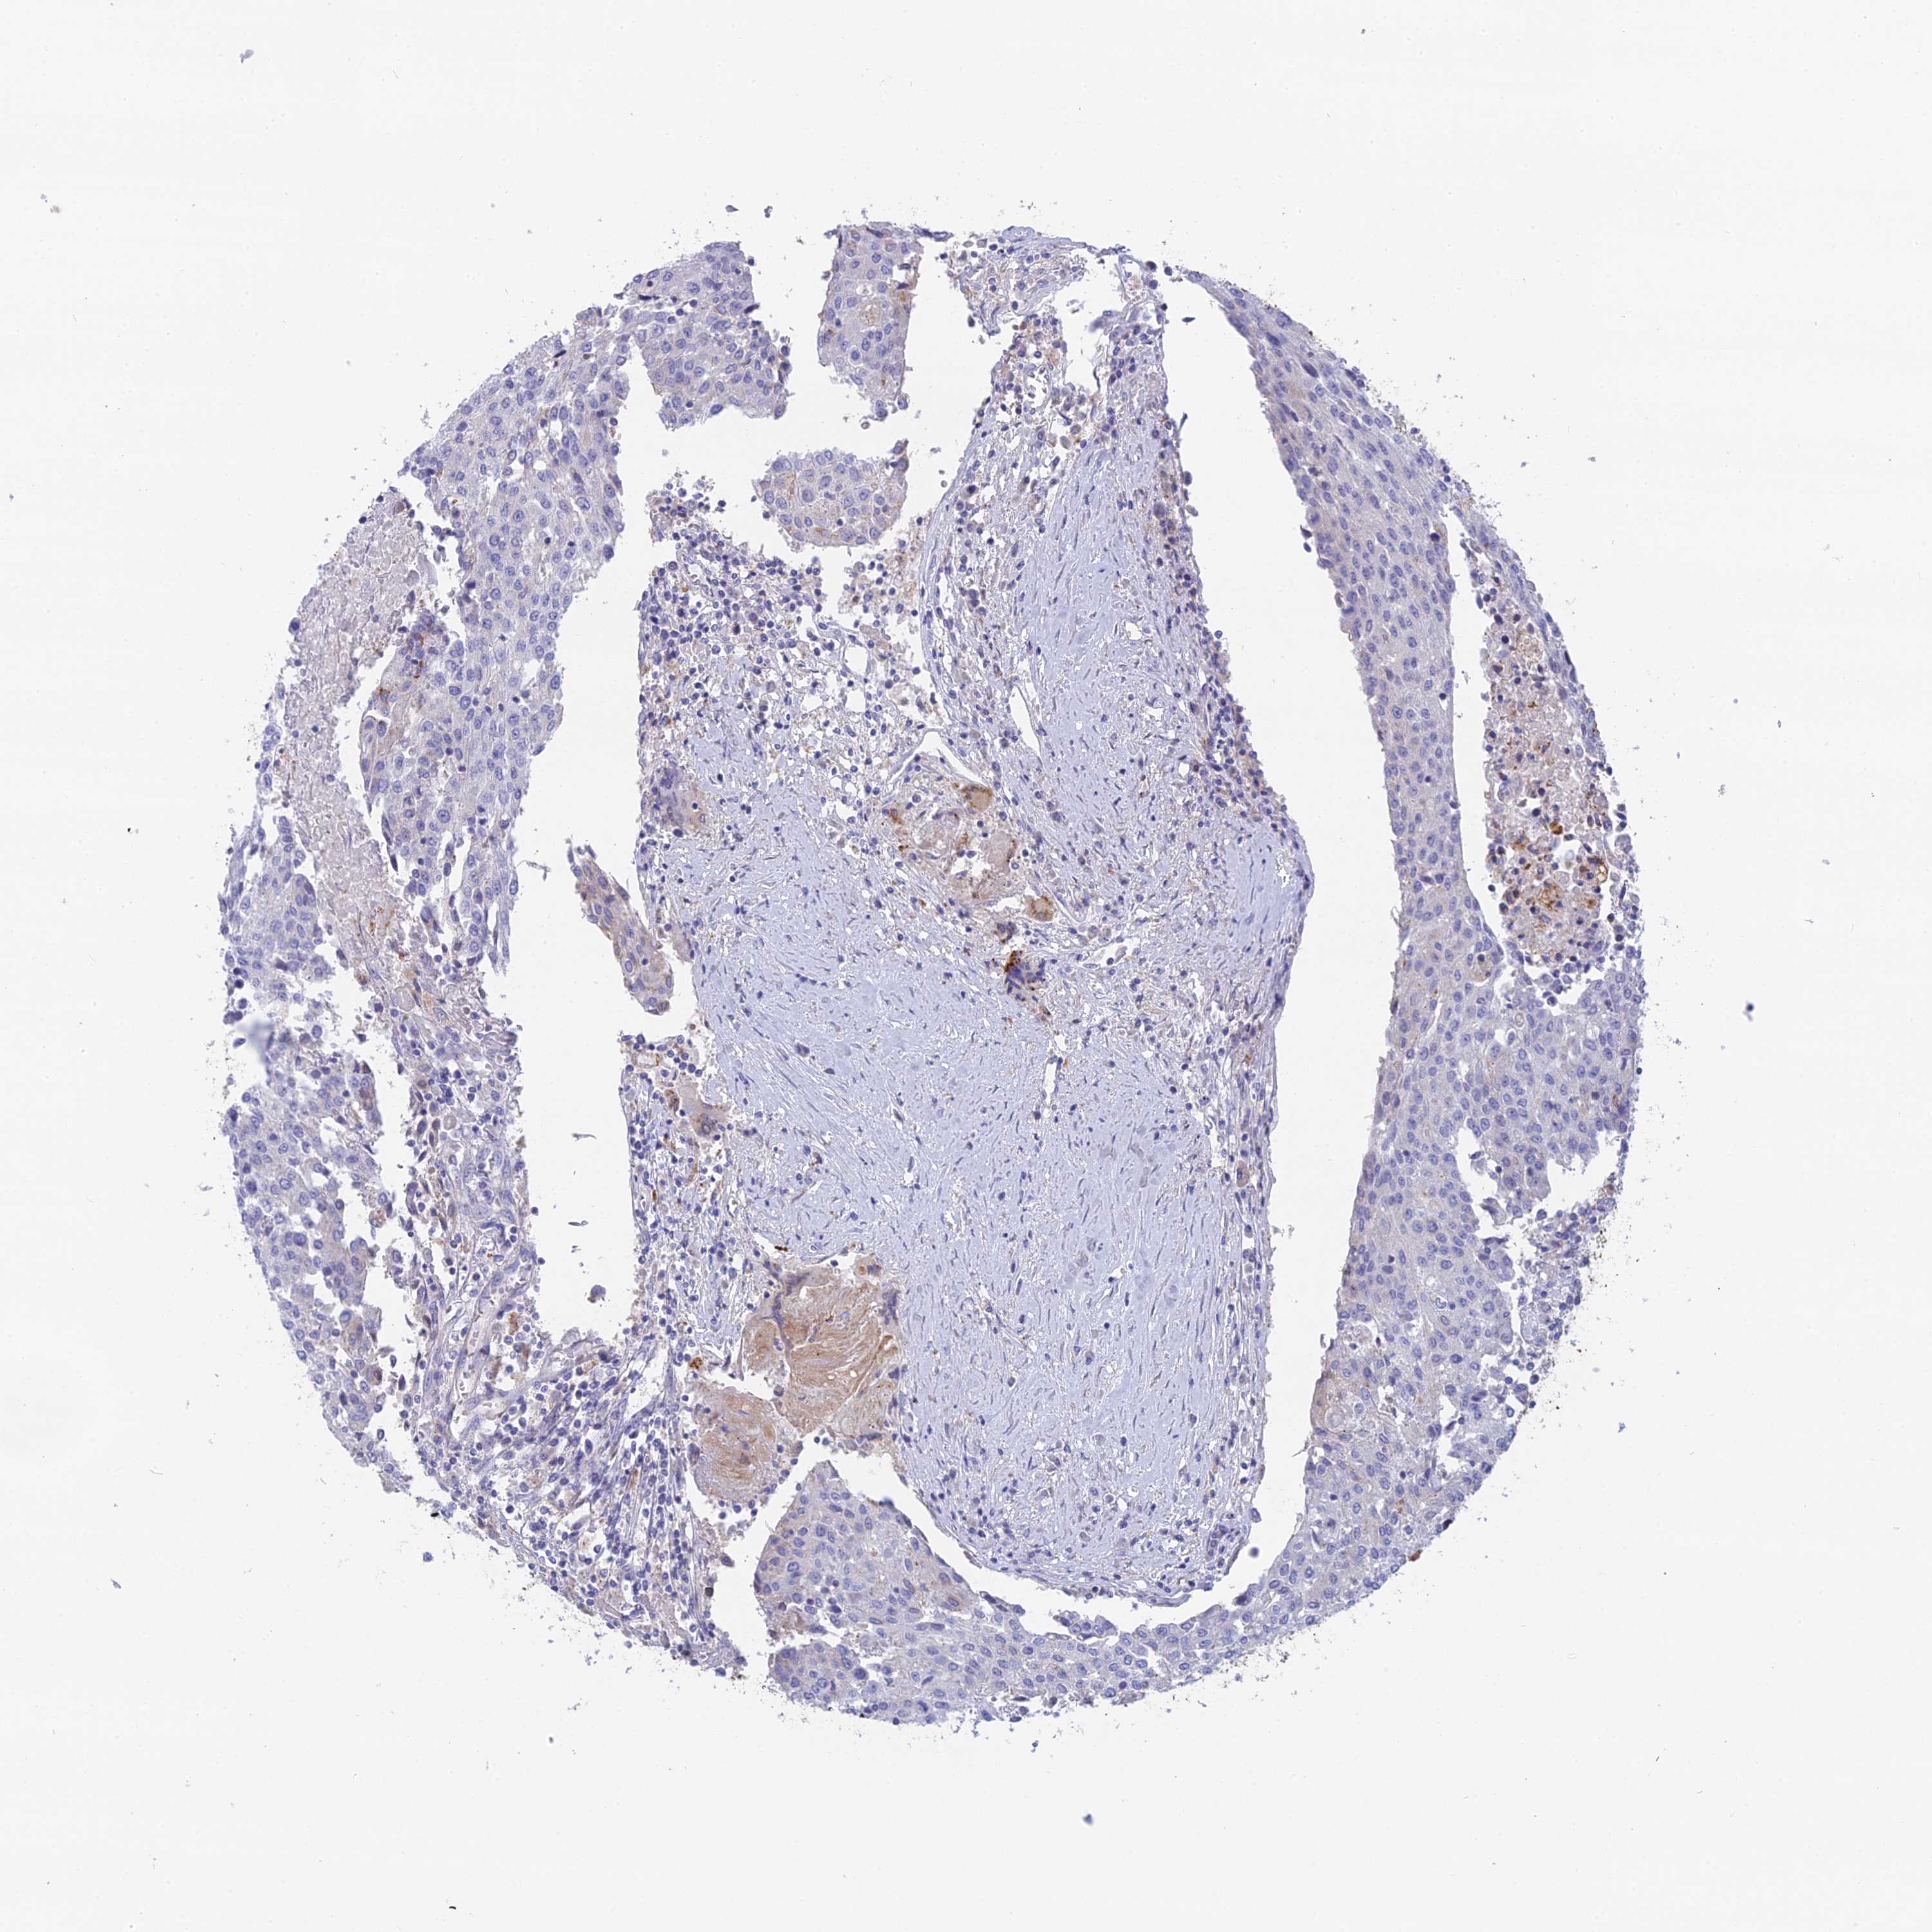

UROTHELIAL CANCER - Protein expressioni

A mouse-over function shows sample information and annotation data. Click on an image to view it in a full screen mode. Samples can be filtered based on level of antibody staining by selecting one or several of the following categories: high, medium, low and not detected. The assay and annotation is described here.

Note that samples used for immunohistochemistry by the Human Protein Atlas do not correspond to samples in the TCGA dataset.

Antibody stainingi

Antibody staining in the annotated cell types in the current human tissue is reported as not detected, low, medium, or high, based on conventional immunohistochemistry profiling in selected tissues. This score is based on the combination of the staining intensity and fraction of stained cells.

Each image is clickable and will lead to virtual microscopy that enables deeper exploration of all samples and also displays staining intensity scores, fraction scores and subcellular localization as well as patient and tissue information for each sample.

Antibody HPA042622

Staining

High

Medium

Low

Not detected

Intensity

Strong

Moderate

Weak

Negative

Quantity

>75%

75%-25%

<25%

None

Location

Urothelial carcinoma, High grade

Urothelial carcinoma, Low grade